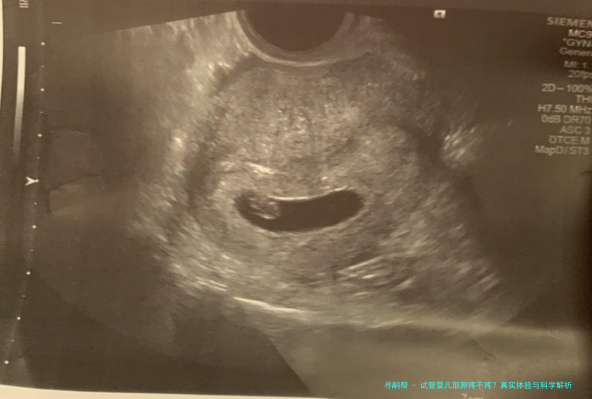

说到身体感受,取卵过程通常是在B超引导下进行的,医生会用一根细针通过阴道穿刺到卵巢,把成熟的卵子吸出来。这听起来可能有点吓人,但实际上,很多女性反馈感觉更像是月经来时的轻微胀痛或痉挛,持续时间很短,也就几分钟的事儿。当然,也有姐妹说几乎没感觉,睡一觉就完成了。疼痛程度跟个人体质、卵泡数量有关,比如卵泡多的话,可能胀感明显些,但一般不会剧痛到无法忍受。我自己听医生朋友讲,大多数患者术后都说:“哎呀,比预想的轻松多了!”这种反馈挺常见的。

从医学角度看,取卵为什么会疼呢?主要是卵巢表面神经比较丰富,穿刺时自然会有些刺激。不过,现在试管婴儿技术很先进,取卵前通常会使用麻醉或镇静措施。比如,局部麻醉可以麻痹穿刺区域,静脉镇静则让你在浅睡眠中度过,醒来后记忆模糊,疼痛感大大降低。另外,取卵前的促排卵阶段,注射药物可能会让卵巢有点胀,但这属于正常反应,取卵时反而能缓解一些。医学上,疼痛管理已经做得很到位,所以别太担心,专业团队会帮你把关的。